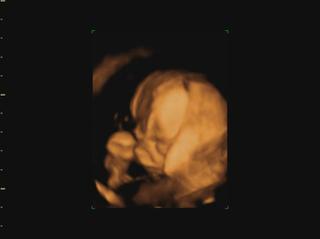

Ahojte kočky, konečne mam trošku času tak si idem spätne prečítať čo ste napísali... a pochváliť vám krásne brušinká 😀 medzi tým Vám pridám moje brušo a našu Izzy neposednú. Máme aj video, ale to som dala len FB, lebo tu sa pridať nedá. Fotky aj video je trochu rozmazané, lebo mala v kuse so sebou narabala... a ano pipik nam nedorastol... 😀